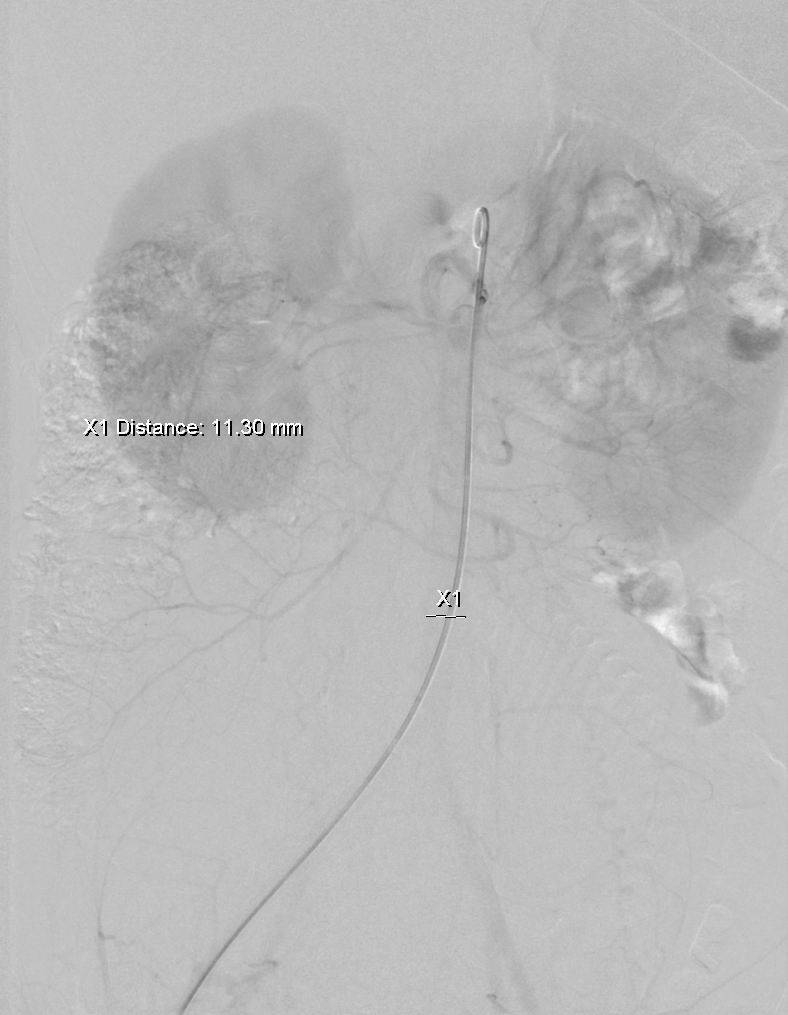

在DSA下能清楚的看到子宫中胎儿的形状(脊柱、颅脑、四肢),还不停的在胎动。介入治疗用明胶海绵栓塞双侧子宫动脉减少子宫的供血图一(左侧子宫动脉栓塞前后,右侧同左侧)。

图一:左侧子宫动脉栓塞前

图一:左侧子宫动脉栓塞后